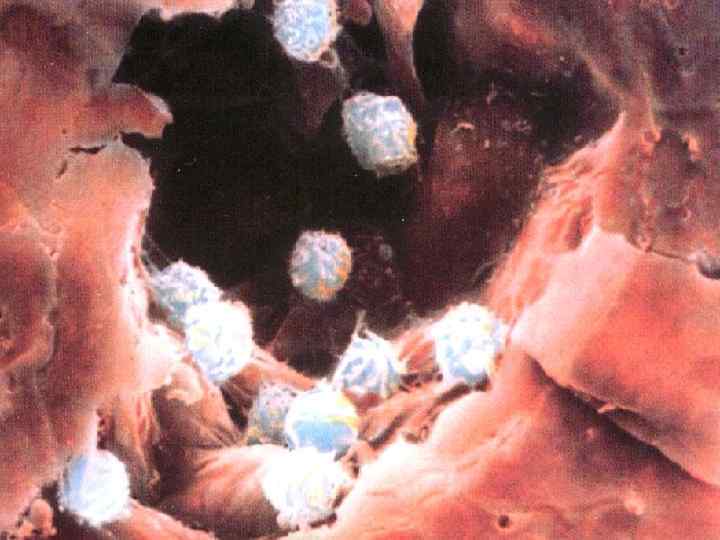

Патогенез ТЭЛА

Патогенез ТЭЛА